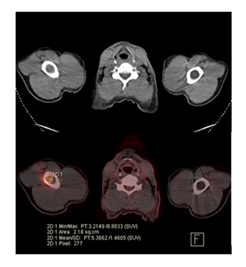

A 70-year-old male patient visited the outpatient clinic with a past medical record of diabetes type II, arterial hypertension under treatment and a history of three months with fatigue, nonproductive cough and dyspnea. During the clinical examination the patient was found to be afebrile and presented on auscultation with respiratory wheezing and presence of abundant crackles in the left hemithorax. The patient’s blood test showed mild anemia with a hemoglobin level 10.9g/dl, the white blood cell count was slightly elevated at 11.8 × 10³/µL due to an increase on neutrophils. Tumor markers showed a CEA (carcinoembryonic antigen) level of 88 U/mL, which is higher than normal. Additional imaging was performed with a chest computed tomography, which revealed a right upper lung solid mass measuring 51x44mm, accompanied with carcinomatous lymphangitis. The patent underwent an 18F-FDG PET/CT scan to assess the extent of the disease. In addition to the pulmonary lesion and carcinomatous lymphangitis, bone lesions were also identified. There were two lesions, one in the right humeral diaphysis, with high radiotracer uptake, (SUV max 8.8), and another in the left iliac bone with similar characteristics (SUV max 14.2). These lesions are PET positive, but not visible on computed tomography, suggesting early bone metastases.